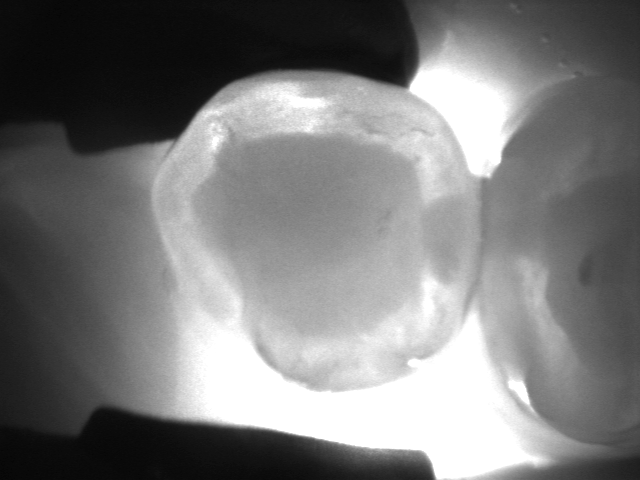

La videocamera digitale sulla testa del manipolo rileva luci ed ombre all’interno del dente e proietta l’immagine ottenuta sullo schermo del pc in tempo reale: le parti sane, che consentono il passaggio della luce, risultano chiare, quelle lesionate, che al contrario lo bloccano, si distinguono nettamente come aree scure.

Le immagini in bianco e nero, altamente dettagliate, ricordano molto le radiografie ma di fatto sono state del tutto ottenute senza radiazioni, soltanto per transilluminazione laser!

Vedere l’estensione della lesione, se ancora soltanto sullo smalto o già sconfinata in dentina, e la sua esatta posizione sono informazioni fondamentali per impostare una terapia che sia il più possibile conservativa.

I fermo immagine ottenuti servono a motivare il paziente e rendere più comprensibile il piano di trattamento. Nel caso di lesioni iniziali permettono, inoltre, un attento monitoraggio nel tempo, ad ogni successivo controllo.

Consente la diagnosi precoce di cracks (incrinature, fratture), demineralizzazioni e carie (occlusale, prossimale o secondaria sotto vecchi restauri), quando sono sopragengivali.

Evidenzia la carie con più sensibilità e attendibilità della sola ispezione visiva e molto prima che appaia alle radiografie, rendendo possibili trattamenti profilattici o minimamente invasivi.